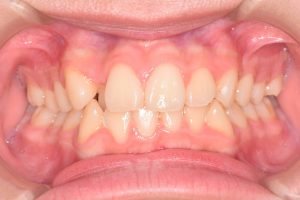

この患者さんは、初診時12才女性。

「上の前歯の中心がずれている」

「全体的に歯並びが良くないのが気になる」

ということで来院されました。

保定開始時(2025年1月)の写真です。

正面

すでに乳歯は1本もありませんでしたが

12歳とまだ若く

骨格的な歯列弓の拡大が期待できること